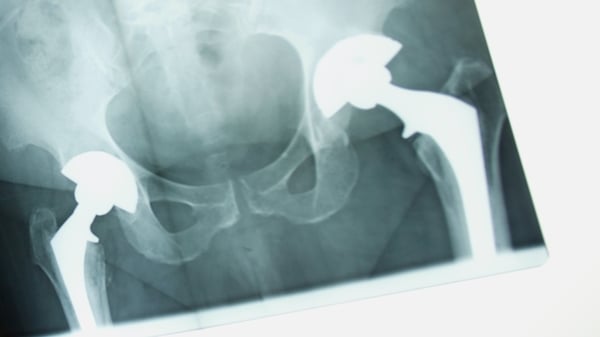

This is caused by the metal on metal contact between the ball and socket of the hip implant, which generates a fine metallic dust within the patient's own body and can cause inflammation around the joint and other health problems.

Last August, DePuy orthopaedics ordered a worldwide recall of its hip implant.